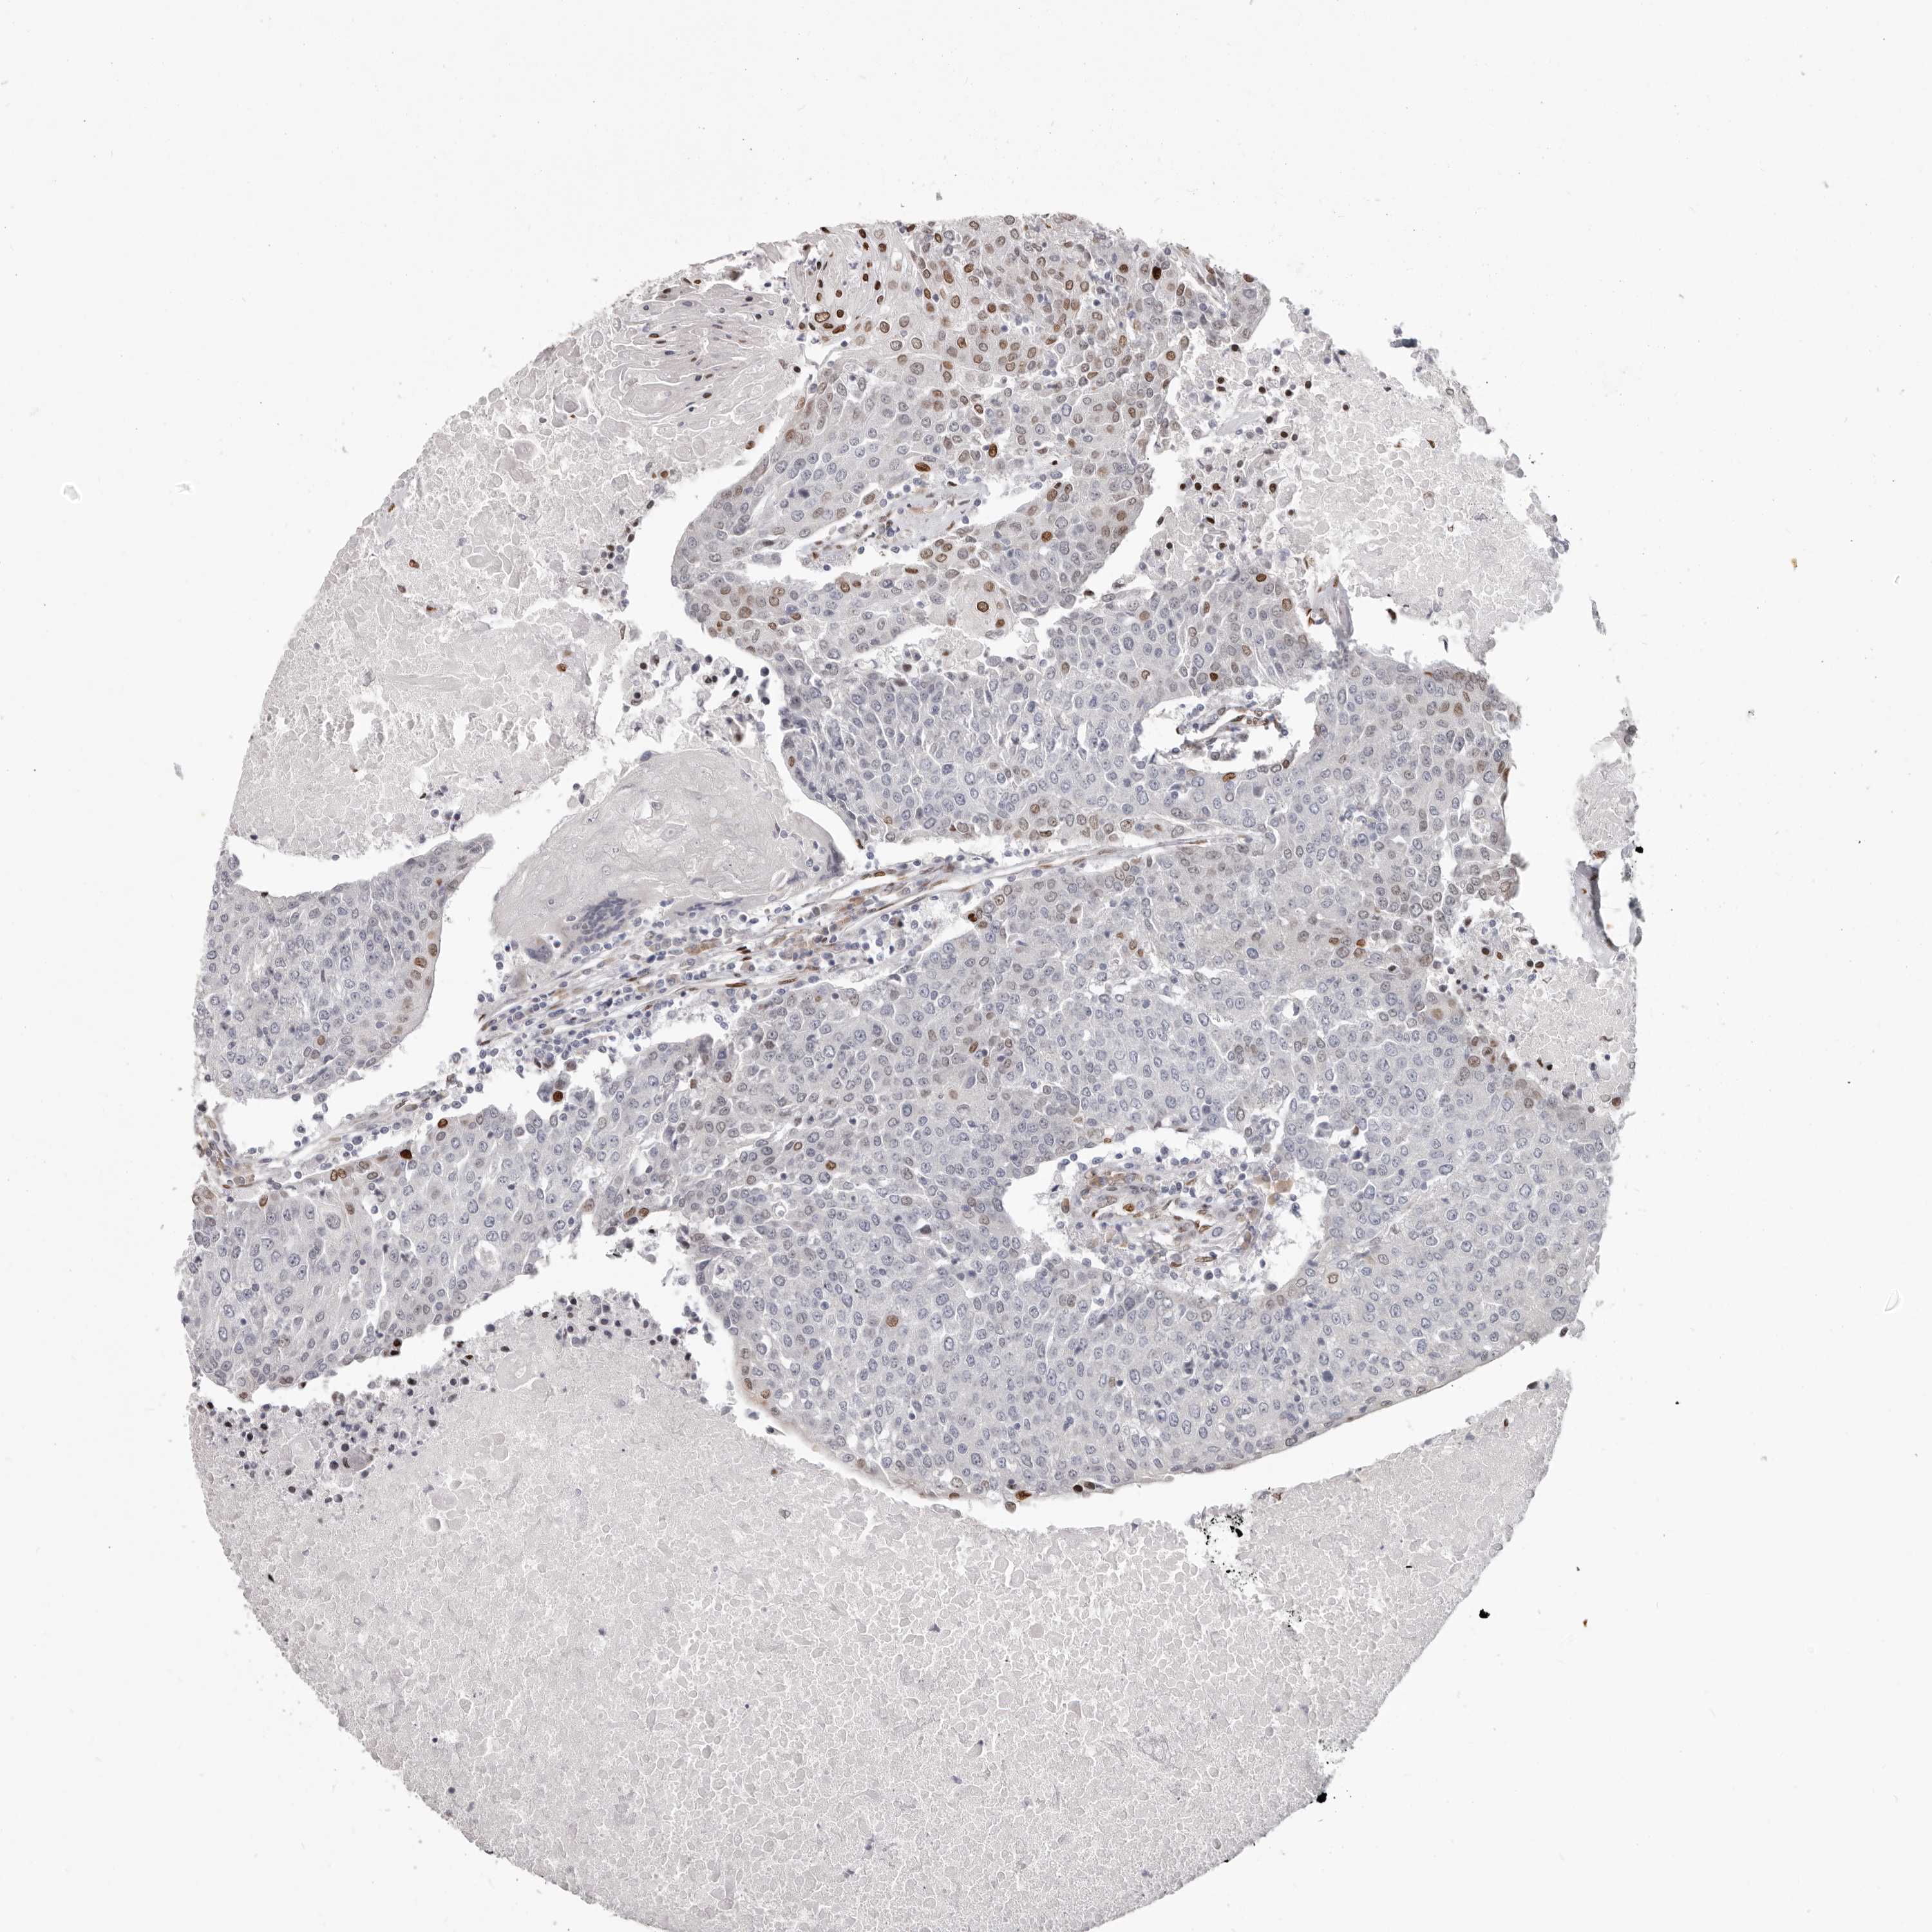

UROTHELIAL CANCER - Protein expressioni

A mouse-over function shows sample information and annotation data. Click on an image to view it in a full screen mode. Samples can be filtered based on level of antibody staining by selecting one or several of the following categories: high, medium, low and not detected. The assay and annotation is described here.

Note that samples used for immunohistochemistry by the Human Protein Atlas do not correspond to samples in the TCGA dataset.

Antibody stainingi

Antibody staining in the annotated cell types in the current human tissue is reported as not detected, low, medium, or high, based on conventional immunohistochemistry profiling in selected tissues. This score is based on the combination of the staining intensity and fraction of stained cells.

Each image is clickable and will lead to virtual microscopy that enables deeper exploration of all samples and also displays staining intensity scores, fraction scores and subcellular localization as well as patient and tissue information for each sample.

Antibody HPA029272

Staining

High

Medium

Low

Not detected

Intensity

Strong

Moderate

Weak

Negative

Quantity

>75%

75%-25%

<25%

None

Location

Urothelial carcinoma, Low grade

Urothelial carcinoma, High grade